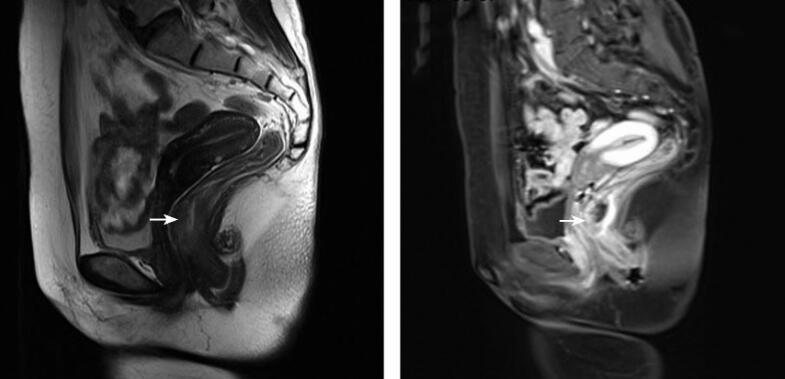

,3~5mm层厚,0.9~1.5mm层间距;DWI(TR/TE=4100ms/85ms,b=800s/mm2);VIBE动态增强加脂肪抑制图像(TR/TE=3.42ms/1.25ms),0.5mm层厚。380×380视野,320×224矩阵。使用钆喷酸葡胺(Magnevist),高压注射器经肘静脉注射,流率为3ml/s,随后再以相同流率注入20ml生理盐水冲刷。动态扫描时间为注射对比剂后15秒、1分钟、3分钟、5分钟共4个时相。总检查时间约为30~40分钟。磁共振成像和病理表现见图1。

直肠癌,T3N1b。

直肠癌是常见消化道恶性肿瘤,发病率仅次于胃和食管癌,近年来发病率有逐年上升趋势,是大肠的最常见部分,占60%左右,大部分在40岁以上,男比女多,抽烟酗酒者易发。通过影像学检查为临床提供一个准确的影像分期和诊断,对评估手术切除的可能性,制订合理的治疗方案以及比较疗效、评估预后等都有非常重要的意义。直肠MRI的临床应用价值主要是定位诊断和确定肿瘤分期。治疗直肠癌的最有效方法是手术切除,而术前准确分期对制订合理治疗方案、选择术式和判断预后均有重要价值。由于MRI的软组织对比分辨力最高,空间分辨力良好,可清楚显示肿瘤大小、浸润深度、与邻近器官关系(包括距离肛缘的距离等),以及周围有无肿大淋巴结等情况。本病通常需要进行平扫加增强扫描。直肠癌在T1WI上信号略低于直肠壁,T2WI上信号略高,增强扫描显著不均匀强化。美国癌症联合委员会(AJCC)/国际抗癌联盟(UICC)结直肠癌TNM分期系统(2010年第七版)是直肠癌分期广泛应用的国际标准。